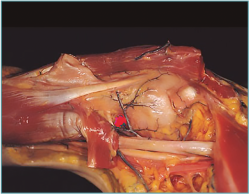

La técnica previamente descrita, por el Dr. Sánchez, se basó en unos estudios anatómicos realizados por este autor junto con el Dr. Gagey en la Universidad R. Descartes de París, donde se realizaron los experimentos, creando patrones de inestabilidad, seccionando de forma progresiva ligamentos y cápsula, y posterior fijación con la técnica (Figura 3). Se demostró que incluso en los patrones más severos de inestabilidad, el sistema funcionaba impidiendo la luxación.

Figura 3. A: patrones de inestabilidad; B: fijación del ligamento en espécimen cadavérico.

En la revista oficial de la Asociación Española de Artroscopia (AEA), Cuadernos de Artroscopia, existen varios trabajos dedicado a los estudios anatómicos y vías de abordaje(17,18) donde se indica el sitio del anclaje del ligamento, tanto en la glena como en el húmero, llegado a la conclusión de que es por dentro de la corredera bicipital y a nivel de los vasos circunflejos el sitio más adecuado (Figura 4).

Figura 4. Preparación anatómica del hombro (Dr. Golanó). Lugar de anclaje del ligamento en el húmero, “punto rojo”.